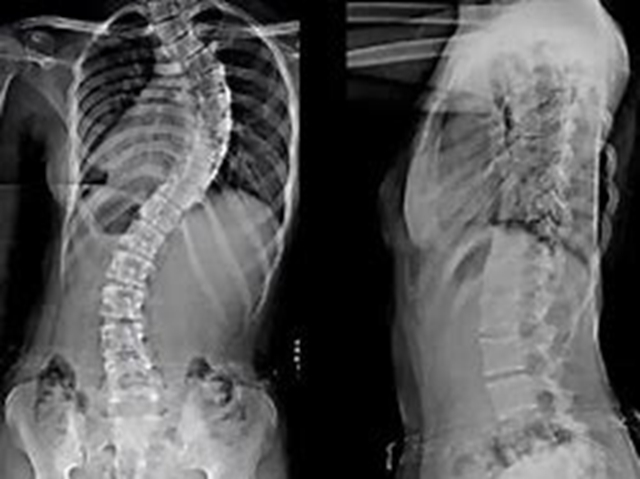

针灸·推拿·康复科主任陈贵全教授介绍:近年来,儿童青少年脊柱侧弯、高低肩、驼背、头部前伸等形体异常问题日益凸显,发病率居高不下。权威数据显示,超过80%的青少年存在不同程度形体不良,多个复合问题的发生率接近70%,严重威胁着青少年的健康成长与未来生活质量。面对这一严峻形势,由重庆市推拿按摩学会牵头,联合区域内相关医疗机构和专业力量,共同发起成立“渝川滇黔儿童青少年形体矫治联盟”。

儿童青少年的脊柱健康关系到他们一生的体态和健康,甚至导致儿童出现自卑等心理问题。脊柱侧弯等形体问题若能早期发现、科学干预,效果显著。